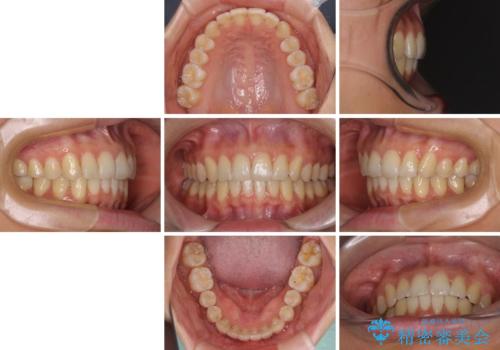

インビザラインによる矯正治療 カリエールディスタライザーを用いた奥歯の咬み合わせ改善

- 前歯の叢生と口元の閉じにくさを気にして来院された患者様です。

奥歯の咬み合わせを見ると、上顎が下顎に対して相対的に前方にありました。

口元の閉じにくさを改善するためには、上顎臼歯を後方に移動させた咬み合わせにする必要があります。

インビザライン単体で改善することも可能ですが、達成する可能性が高くないため、カリエールディスタライザーという補助装置を併用して、より確実性を上げることとしました。

奥歯の咬み合わせを改善しながら、並行してインビザラインで歯列を整えることとしました。

カリエールディスタライザーを併用したことで、確実かつ短期間で治療を終えることができました。